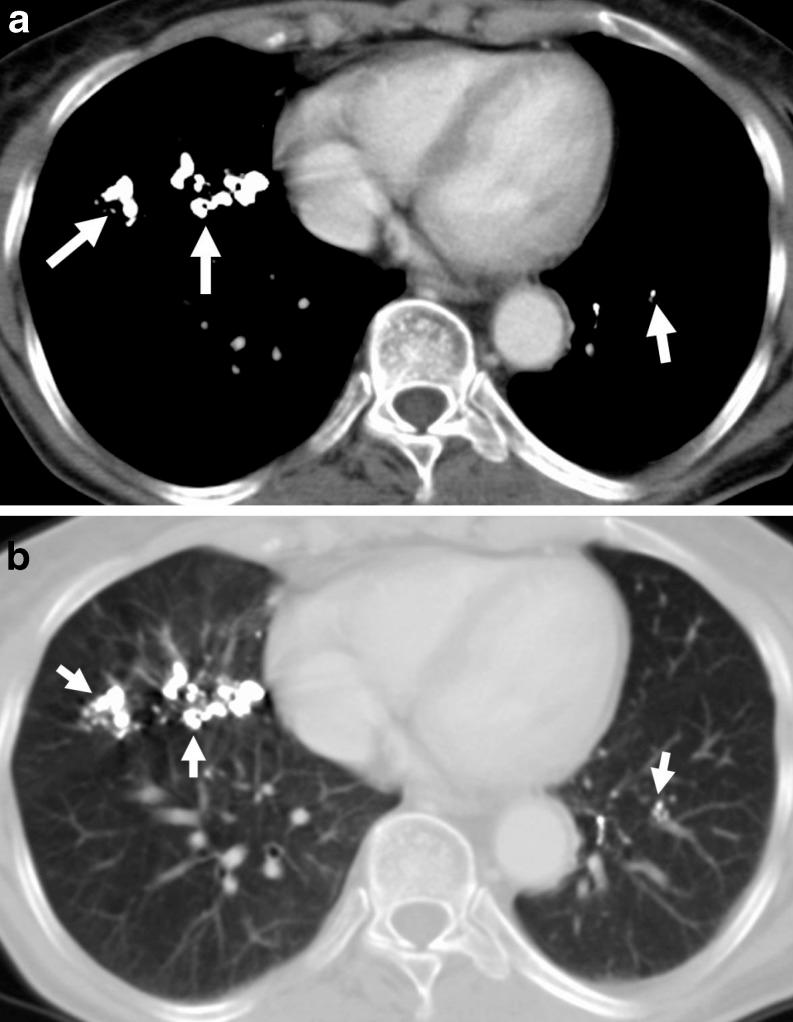

高衰减肺部异常的CT表现

CT findings of high-attenuation pulmonary abnormalities.

目的

回顾常见及不常见的高衰减肺病变的计算机断层扫描(CT)表现,并基于CT表现的模式和分布,提出可导致高衰减肺异常的各种实体的分类方案。背景:肺高衰减异常可由钙沉积引起,或较少见的由其他高衰减物质如滑石粉、胺碘酮、铁、锡、汞和硫酸钡沉积引起。CT对检测肺实质、气道、纵隔和胸膜内异常高衰减区域高度敏感。钙化及其他高衰减情况的病因可根据肺实质内异常的位置和模式以及相关临床特征来确定。结果:我们提出了一种基于CT上高衰减情况的五种主要模式的存在和分布的诊断方法:(1)小的高密度结节,(2)大的钙化结节或肿块,(3)高衰减线性或网状模式,(4)高衰减实变,(5)高衰减肺外病变。结论:一些肺高衰减异常具有特征性的CT表现,提示正确诊断。在其他疾病中,临床特征和影像学表现相结合可显著提高诊断准确性。